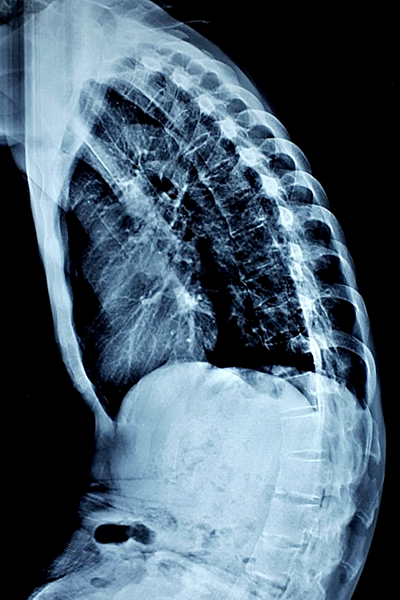

Ảnh chụp X-quang cột sống của bệnh nhân cong, gập trước khi phẫu thuật. Ảnh do bác sĩ cung cấp.

Các bác sĩ Bệnh viện Trung ương Quân đội 108 tiến hành nắn chỉnh biến dạng gù của chàng trai bằng kỹ thuật mới với 4 thanh rod thay vì 2 thanh như trước. Trong đó 2 thanh ngắn cố định từ đốt sống L2 đến L4, 2 thanh dài cố định từ đốt sống T10 đến S1. Kíp phẫu thuật đã cắt một phần đốt sống L3 để nắn chỉnh lại cột sống đã biến dạng.